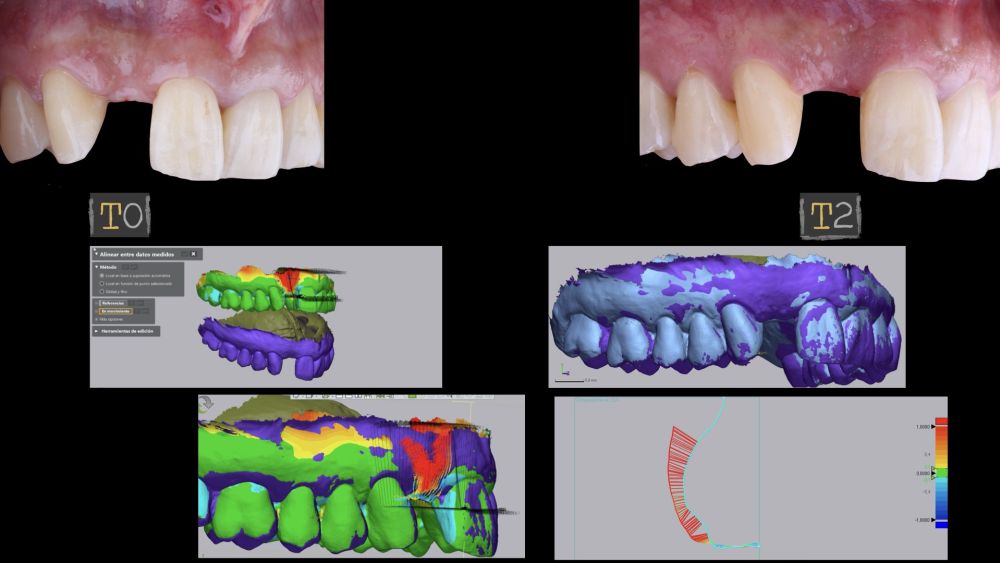

The site where the surgery was performed (implant 1.2), together with its complete arch, was scanned using an

intraoral optical scanner at different time points; three

weeks before the surgery (T0), immediately after the surgery (T1), and one and a half months post-surgery (T2). The generated digital models were exported and saved as STL files to be subsequently imported into image analysis software (Geomagic® Control X™; 3D

Systems, Rockhill, SC). An analysis of preoperative (T0) versus postoperative (T1 and T2) thickness changes was conducted. These longitudinal thickness changes were analysed on the vestibular aspect of the implantsupported crown using the “3D Compare” function, which

enabled the creation of a colour map following model superimposition to quantitatively assess the variations occurring in the intervention areas. The colour map ranges from +3 mm to -3 mm, with a tolerance of ± 0.15mm, and is interpreted as follows: green areas correspond

to perfect alignment of the models; red, orange, and yellow colours are interpreted as volume gain, while dark and light blue colours respectively represent volumetric loss (Figures

8 and 9). Subsequently, a rectangular region of interest was designed to study the intervention area, where linear changes of the peri-implant mucosa were evaluated (Figures 8 and 9). The horizontal extension of the region of interest encompassed both papillae (mesial and distal), covering the marginal contour of the implant crown up to the marginal surface of the adjacent teeth. To report the results of interest, points were identified on the horizontal plane previously designed on the vestibular aspect of the implant, starting from the mesial and extending 0.5 mm distally. Positive values indicated that the peri-implant soft tissues were located more buccally (> thickness), whereas negative values indicated that the peri-implant soft tissues were located more palatally (< thickness).

The final clinical outcome was satisfactory, fulfilling the patient’s aesthetic requirements. The soft tissues were morphologically and dimensionally stable, with no signs of

inflammation. However, changes in the peri-implant soft tissue (vestibular volumetric thickness) were demonstrated both qualitatively and quantitatively (Figures 8 and 9). In the immediate postoperative period (T1), the mean gain obtained when comparing T0 to T1 was 0.88 ± 0.15 mm, with a maximum increase of 1.1 mm. When comparing T0– T2, a mean gain of 0.73 ± 0.23 mm was observed. That is,

a volume contraction of 0.16 mm occurred from the time of graft placement (T1) until one and a half months later (T2).